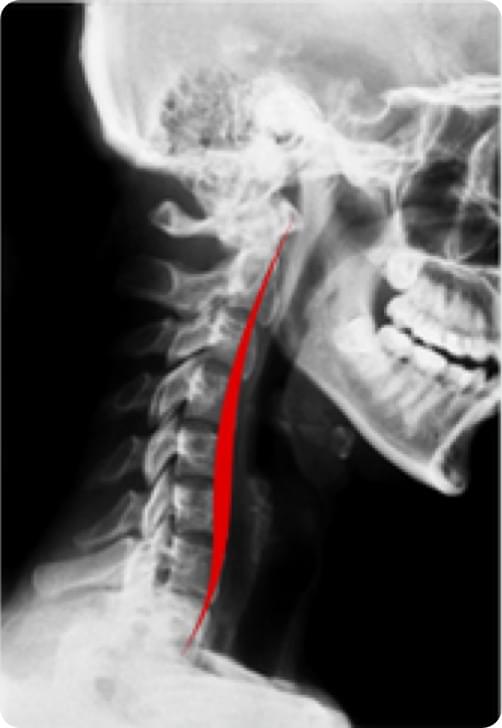

颈椎反弓、变直